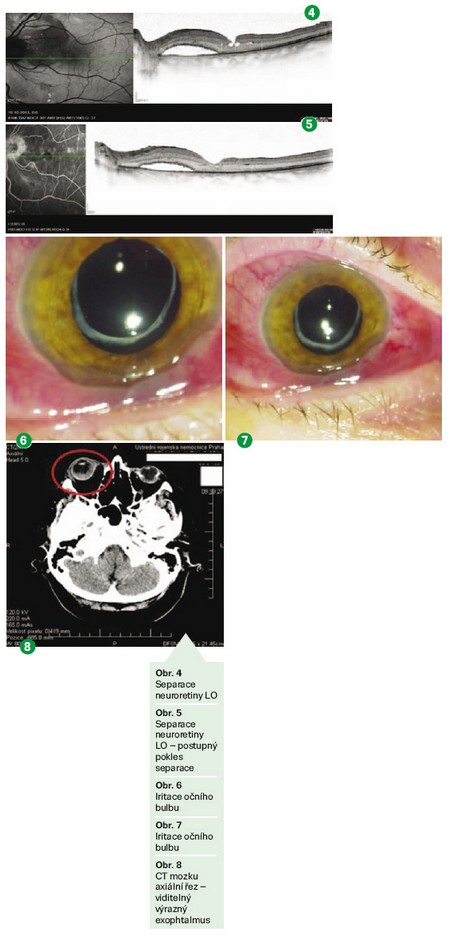

Následovalo sedm pooperačních kontrol – prováděny opakovaně OCT s nálezem separace neuroretiny (obr. 4), se stále přítomnou subretinální tekutinou. U jednotlivých kontrol postupně dochází k poklesu separace (obr. 5). V březnu 2014 se stav stabilizoval, není nutná chirurgická intervence, doporučená kontrola za rok.

V červnu 2014 přichází pacientka pro subjektivní zhoršení stavu – cca 10 dnů má potíže na PO – zarudnutí (obr. 6, 7), nemůže otevřít víčko, trpí bolestí hlavy.

Vzhledem k nejasné etiologii nemoci a stále se zhoršujícím subjektivním i objektivním příznakům je u pacientky opět vyžádáno CT orbity a mozku s kontrastem ve STATIMOVÉM REŽIMU (obr. 8). Endokrinologické vyšetření a ORL konzilium bylo součástí žádosti.